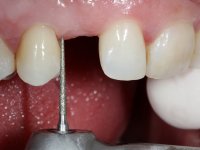

To define the dental zone to be covered by the Maryland bridge retainers, the patient was asked to perform maximum intercuspidation movements, and the contact points were marked with articular paper. Tooth preparation of the interproximal surfaces was made, to create a prosthetic insertion axis. It was sought that the mesio-distal diameter at the incisal level was equal to the diameter mesio-distal at the cervical level, that is to say, the interproximal walls were parallelized. Tooth preparation was done with fine grain diamond drills, and later polishing was done with abrasive discs. Color information was collected even before confection of the impression, to avoid dehydration of the arcade. Definitive impression was made using wash technique impression with silicone of heavy and regular consistency, both with fast setting, and a working plaster model was prepared in the lab. A laboratory scanner was used to scan the working model, and later, the infrastructure for the Maryland bridge was made using a CAD-CAM process. Ceramic was placed on this subframe. A ceramic adhesive was applied to the internal surface of the wings and connectors, which would enable bonding to the adjacent teeth. The adhesive bridge was bonded in the mouth following the conventional bonding technique. After bonding, the protrusion and laterality movements were carefully checked to avoid undesirable contacts.